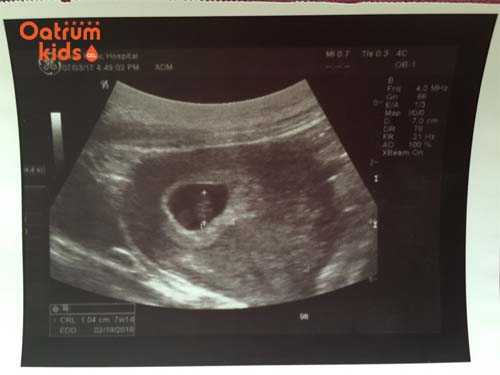

Thai 7 tuần tuổi chưa thể siêu âm được giới tính.

Thai 7 tuần biết trai hay gái chưa?

Mẹ nên lưu ý ở tuần mang thai thứ 7 bộ phận sinh dục của các bé vẫn chưa phát triển đầy đủ nên khó có thể chẩn đoán bào thai là giới tính trai hay gái. Cho nên nếu đi siêu âm sẽ khó có thể phát hiện được mà thường ít nhất từ tuần thứ 12 trở đi mới soi ra được.